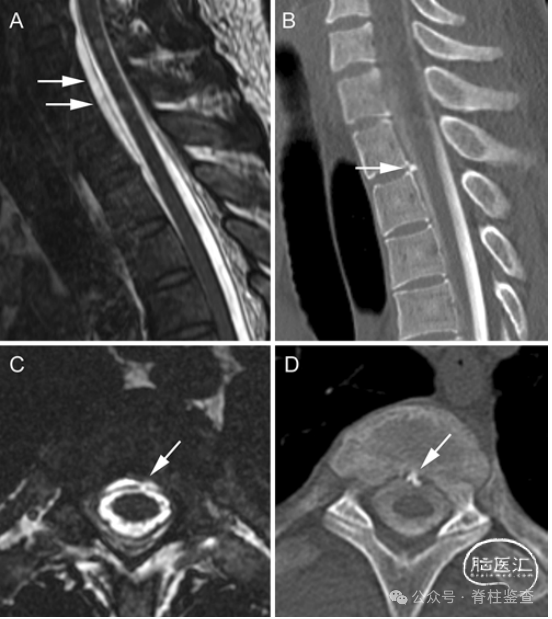

Case 2

一名 30 岁男性因自发性低颅压出现严重的直立性头痛,听力障碍。

腰椎硬膜外补片治疗后未能缓解症状。通过后方硬膜入路切除刺状病变,通过肌肉移植修复腹侧硬膜撕裂。术后,患者的症状完全恢复。